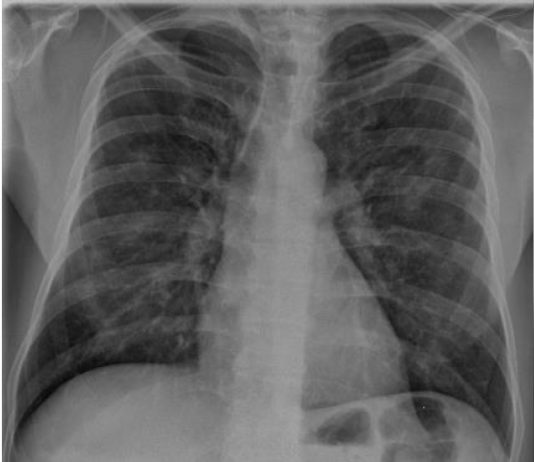

47-year-old male

patient with asthenia, arthralgia, headache, sick cough and fever 39°C since

March 1 presented to the ED on...